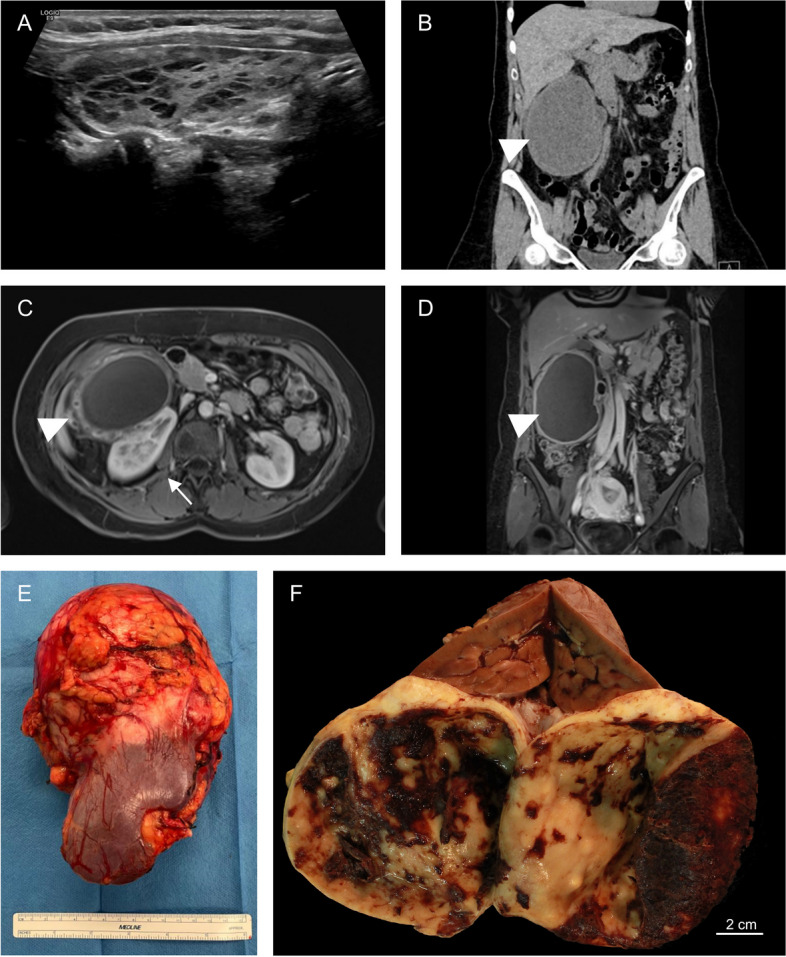

Background: Retroperitoneal dedifferentiated liposarcoma is a rare, aggressive malignancy, characterized by high rates of recurrences and the potential for metastasis. On imaging, these tumors typically present as a solid mass with lipomatous and non-lipomatous components. Cystic changes of dedifferentiated liposarcomas is exceedingly rare and might pose significant diagnostic challenges, with only a few cases reported in the literature. REPORT OF 2 CASES: We here present two cases of retroperitoneal dedifferentiated liposarcoma with a rare cystic presentation in two female patients aged 51 and 62 years. Imaging revealed large perinephric cystic masses measuring up to 13.0 cm and 16.1 cm, respectively, with calcifications of the cyst wall observed in the second case. Differential diagnoses included cystic echinococcosis, mesenchymal neoplasms, and benign cystic lesions (e.g. endometrial cyst). Both patients underwent upfront compartmental en-bloc surgical resection of the tumor mass and the kidney after multidisciplinary tumor board (MDT) discussion. Macroscopically, the tumors were adherent to but sharply demarcated from the kidney. Histological examination of the first case revealed a small component of well-differentiated liposarcoma (WDLPS) adjacent to a large non-lipogenic sarcoma with a prominent whirling pattern, compatible with dedifferentiation. The second case demonstrated a spindle cell neoplasm with prominent osteosarcomatous heterologous differentiation. MDM2 amplification was confirmed in both cases by molecular testing. No long-term follow-up data is available for either patient.

Conclusion: In conclusion, these cases highlight the importance of recognizing unusual and extensive cystic changes of dedifferentiated liposarcoma, which can complicate the diagnostic work-up.